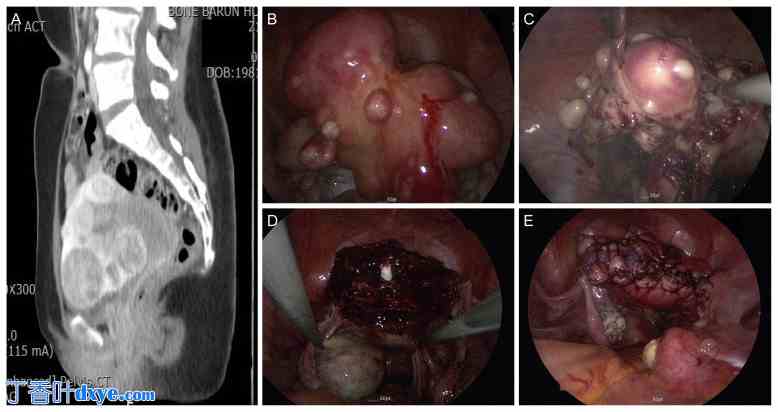

子宫底切除术是一种外科手术方法,它采用现有的子宫肌瘤切除术,同时切除位于子宫底部的发育性肌瘤以及子宫体部和下段的肌瘤。这种方法可以缩短手术时间并最大限度地减少出血(图2)。特别是当子宫体积较大、合并子宫腺肌症或子宫黏膜下肌瘤时,子宫底切除术被认为是一种合适的手术方法。该方法通过减少手术切口、缝合以及在术中切断子宫动脉升支来减少出血。此外,在合并盆腔子宫内膜异位症的情况下,通过切除肌瘤和部分子宫组织来缩小子宫体积,有助于明确手术视野。当需要同时进行粘连分离术或深部浸润性盆腔子宫内膜异位症手术时,子宫底切除术被认为可以提高手术效果。

图2.

2.jpg

单孔腹腔镜下子宫底切除术术前和术后状态(A-E)。(A)术前盆腔CT(矢状位)。(B)多发性肌瘤(术前)。(C)子宫底楔形切除。(D)子宫内膜缝合。(E)双层子宫肌层缝合。CT,计算机断层扫描。